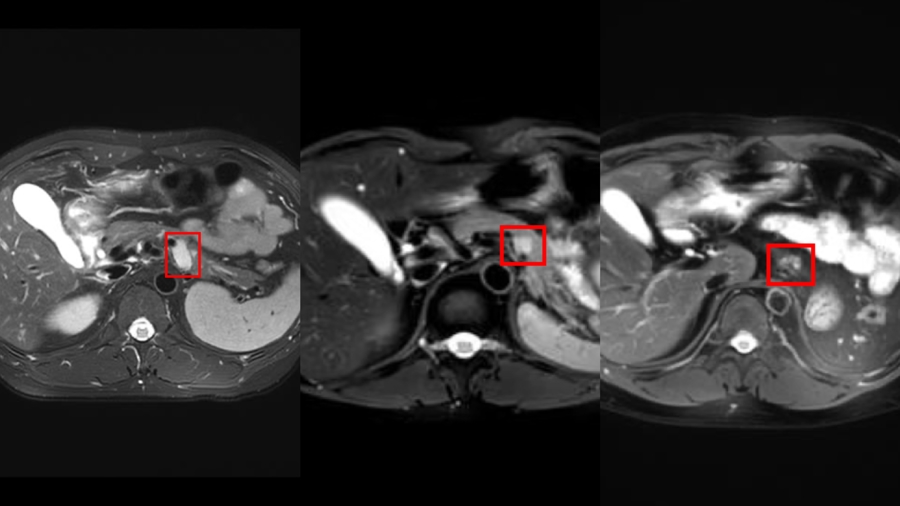

诊治前、疫苗前/后 影像图

宏泰配资尔后,张先生每三周注射一次疫苗。原操办九周期的诊治,因肿瘤执续减轻得以继续;完成16次注射后,他的靶病灶显然减轻,全身无新发病灶,ACTH、皮质醇等激素水平经替代诊治趋于清醒。这场改造诊治,不仅为张先生重燃生存但愿,也为肾上腺皮质癌的精确诊治开辟了新旅途。他坦言:“每次注射齐是一次告成,能陪着孩子渐渐长大,等于我最大的心愿。”